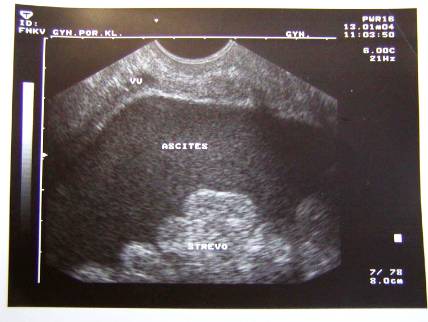

3.Duplicita (pac.M.B.-tu markery, laparotomia, radikální operace pro Ca ovarii, peroperační biopsie)

Duplicita (pac.M.B.-tu markery, laparotomia, radikální operace pro Ca ovarii, peroperační biopsie)

Duplicita(pac.M.B.-tu markery, laparotomia, radikální operace pro Ca ovarii, peroperační biopsie)

Duplicita (pac.M.B -laparotomia, radikální operace pro Ca ovarii, peroperační biopsie)